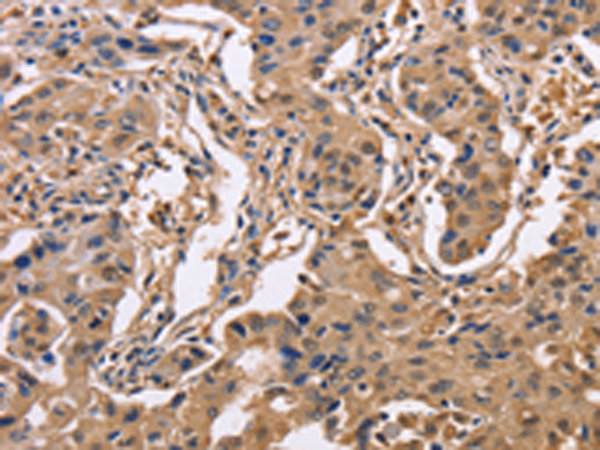

分类: 科研抗体货号: P07985别名: HXK3; HKIII应用: IHC反应种属: Human, Mouse, Rat